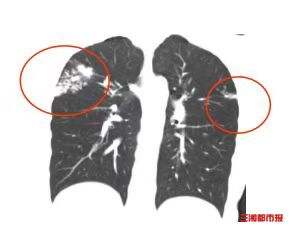

2026年2月,距筛查仅5个月,小东无明显诱因出现咳嗽、低热症状,自行服药后虽体温恢复正常,但咳嗽持续加重,甚至出现痰中带血丝的现象。经医生检查,最终确诊为活动性肺结核。随后不得不办理休学,目前在长沙市中心医院学生儿童结核科接受较长时间的治疗。

潜伏感染者虽“无症状、胸片正常”,但一旦因熬夜、劳累、营养不足等导致免疫力下降,结核菌便可能大量繁殖,引发疾病。小东的遭遇,正是忽视了“筛查—评估—干预—随访”全流程规范治疗所导致。